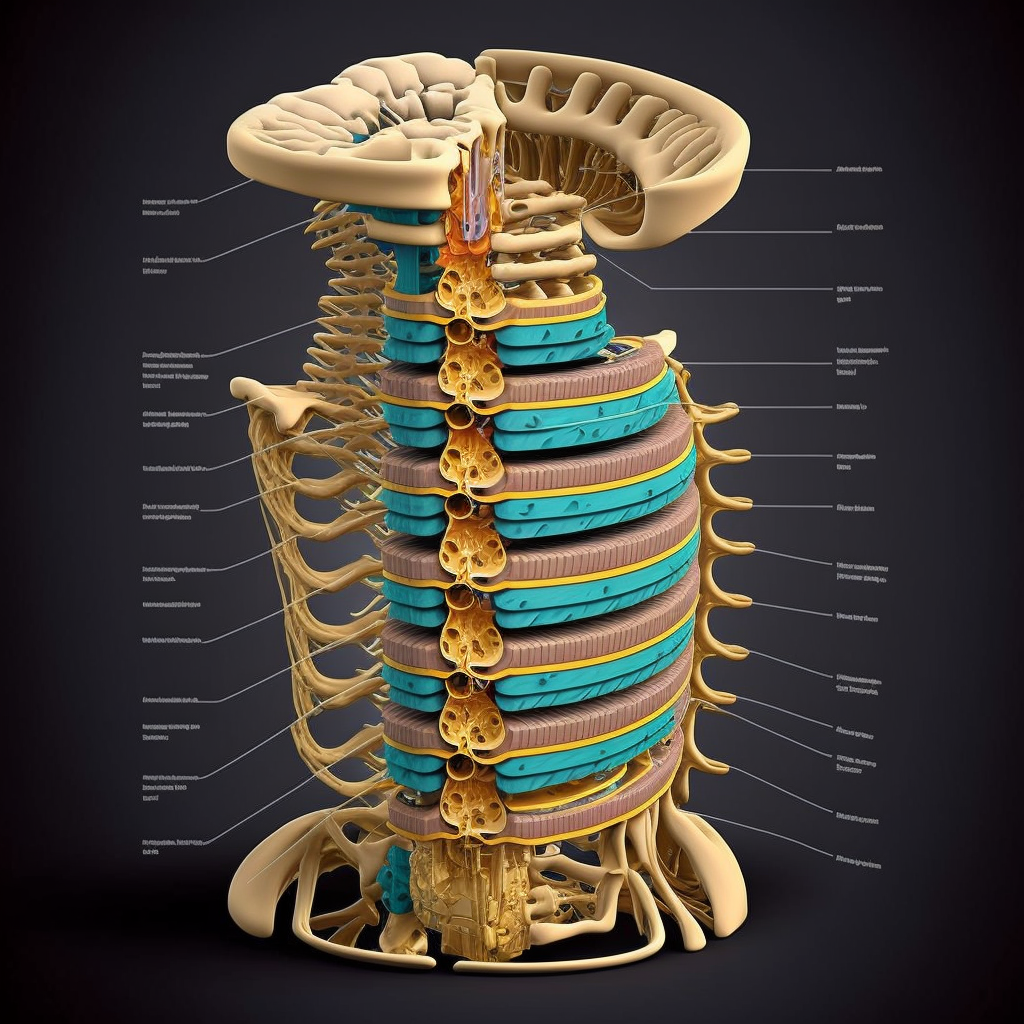

Diz ağrısı, farklı artrit türlerinden kaynaklanabilen yaygın bir şikayettir. Artrit, eklemlerde ağrı, şişlik ve sertliğe neden olan bir iltihaplanmadır. Dizi etkileyen en yaygın artrit türü, kemikler arasındaki kıkırdağın aşındığı osteoartrittir. Diğer formlar arasında eklemlere saldıran otoimmün bir hastalık olan romatoid artrit ve dizdeki bir yaralanmadan sonra ortaya çıkan travma sonrası artrit yer alır.

Diz artriti, uyluk kemiği ile kaval kemiği arasındaki eklemi etkileyen bir durumdur. Dizde ağrı, sertlik, şişlik ve hareket kabiliyetinde azalmaya neden olabilir. Osteoartrit, romatoid artrit ve travma sonrası artrit gibi farklı diz artriti türleri vardır. Her türün farklı nedenleri ve semptomları vardır.

Osteoartrit en yaygın diz artriti türüdür. Eklemi yastıklayan kıkırdak zamanla aşınarak kemik-kemik temasına yol açtığında ortaya çıkar. Bu durum iltihaplanmaya, ağrıya ve hareket açıklığının azalmasına neden olur. Osteoartrit genellikle 50 yaşın üzerindeki kişileri etkiler ve kadınlarda erkeklerden daha yaygındır.

Romatoid artrit, eklemlerde kronik iltihaplanmaya neden olan otoimmün bir hastalıktır. Vücuttaki herhangi bir eklemi etkileyebilir, ancak genellikle dizleri tutar. Romatoid artrit etkilenen eklemlerde ağrı, şişlik, sıcaklık ve kızarıklığa neden olabilir. Ayrıca gözler, kalp ve akciğerler gibi diğer organları da etkileyebilir. Romatoid artrit genellikle 30 ila 60 yaş arasındaki kişileri etkiler ve kadınlarda erkeklerden daha yaygındır.

Travma sonrası artrit, dizde kırık, bağ yırtığı veya menisküs hasarı gibi bir yaralanmadan sonra gelişen bir artrit türüdür. Dizde ağrı, sertlik ve dengesizliğe neden olabilir. Travma sonrası artrit her yaşta ortaya çıkabilir ve erkeklerde kadınlardan daha yaygındır.